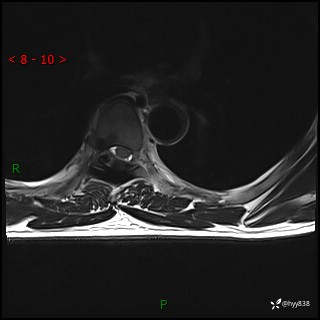

axi T2WI